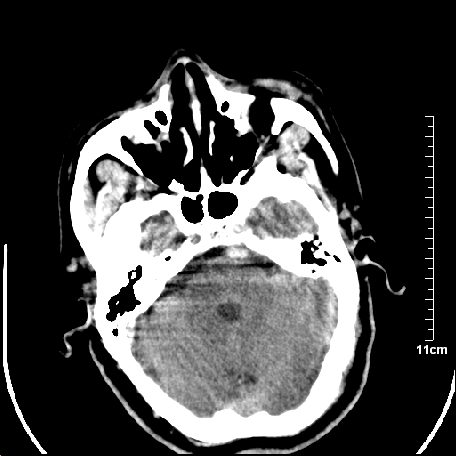

外伤患者,什么病,

外伤患者,没什么症状,

双侧外侧裂,左侧脑沟见高密度结节影,边清,还有鞍上池层面密度也高

脑血管硬化?高血红蛋白症?

高血红蛋白症可能

高血红蛋白症

高血红蛋白血征

基底动脉硬化迂曲。高血红蛋白血症。